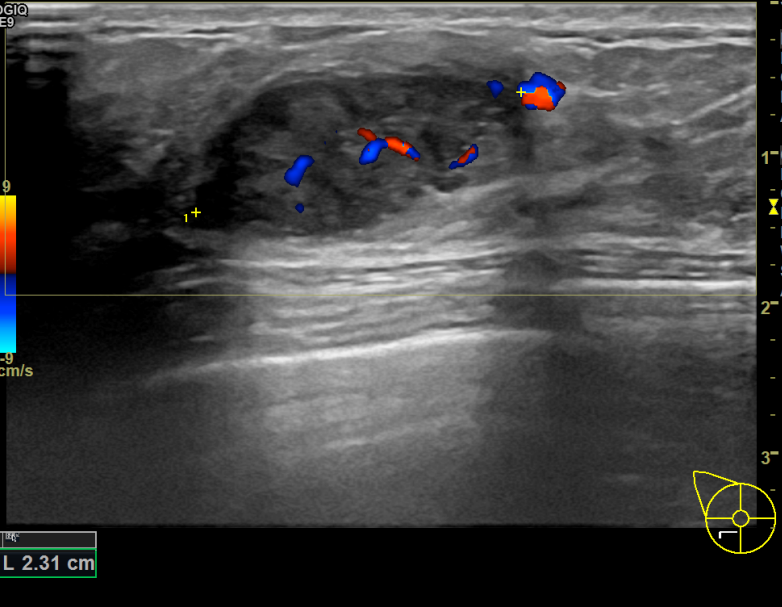

아산유외과개원후 736번째 유방암진단

상기환자 우측에 유방멍울만져져 내원하신 50대 여성분으로 우측유방멍울 조직검사시행후 유방암 진단되었습니다.